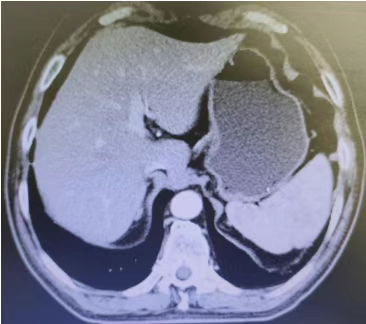

Abdominal CT films (2 sheets) on March 3, 2020